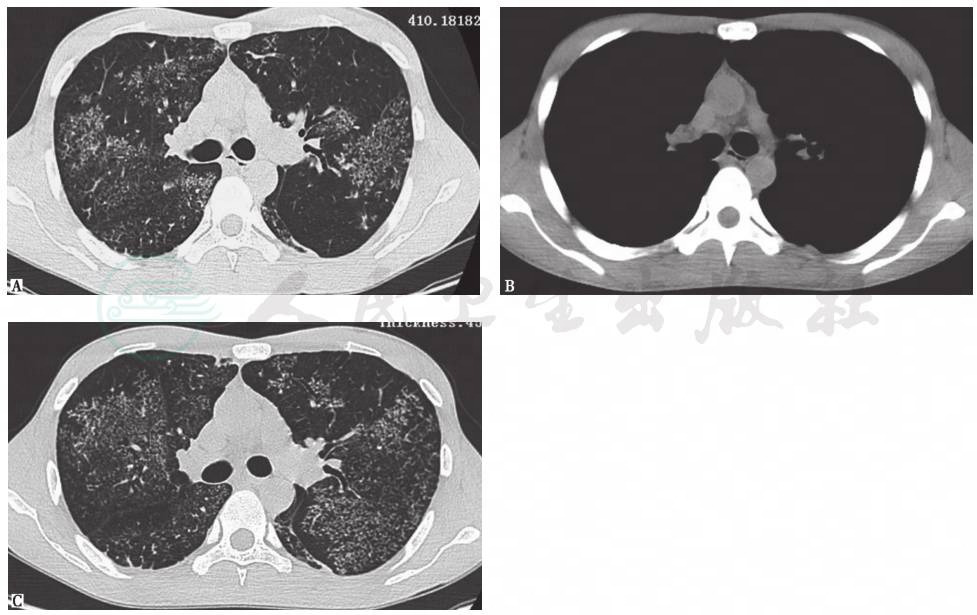

HRCT检查提示弥漫性簇性微结节聚集征以及广泛树芽征,呈地图状分布,纵隔淋巴结肿大 (图1)。

图1 不同病程阶段胸部HRCT表现

HRCT可见双肺弥漫性簇性微结节聚集征以及广泛树芽征,呈地图状分布(A),纵隔淋巴结肿大(B),并且随病程延长(10个月后)肺内类似病变有增多趋势(C)